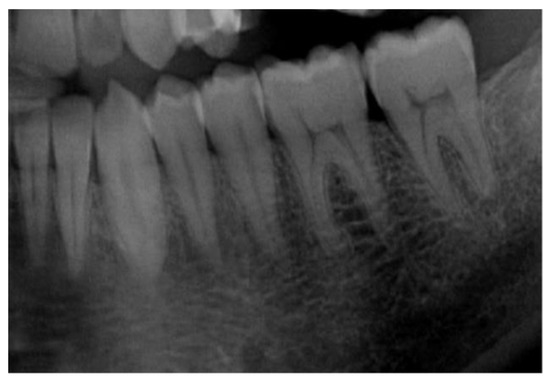

| Input image | Panoramic Radiograph | 2D Panoramic Radiograph images |

| Stages of teeth development | Categorical | Stages of the seven left lower mandibular teeth |